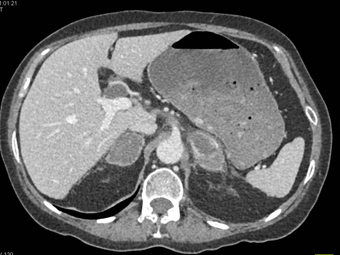

The least likely primary tumor in this case is

metastatic melanoma

lung cancer (NSCL)

colon cancer

renal carcinoma